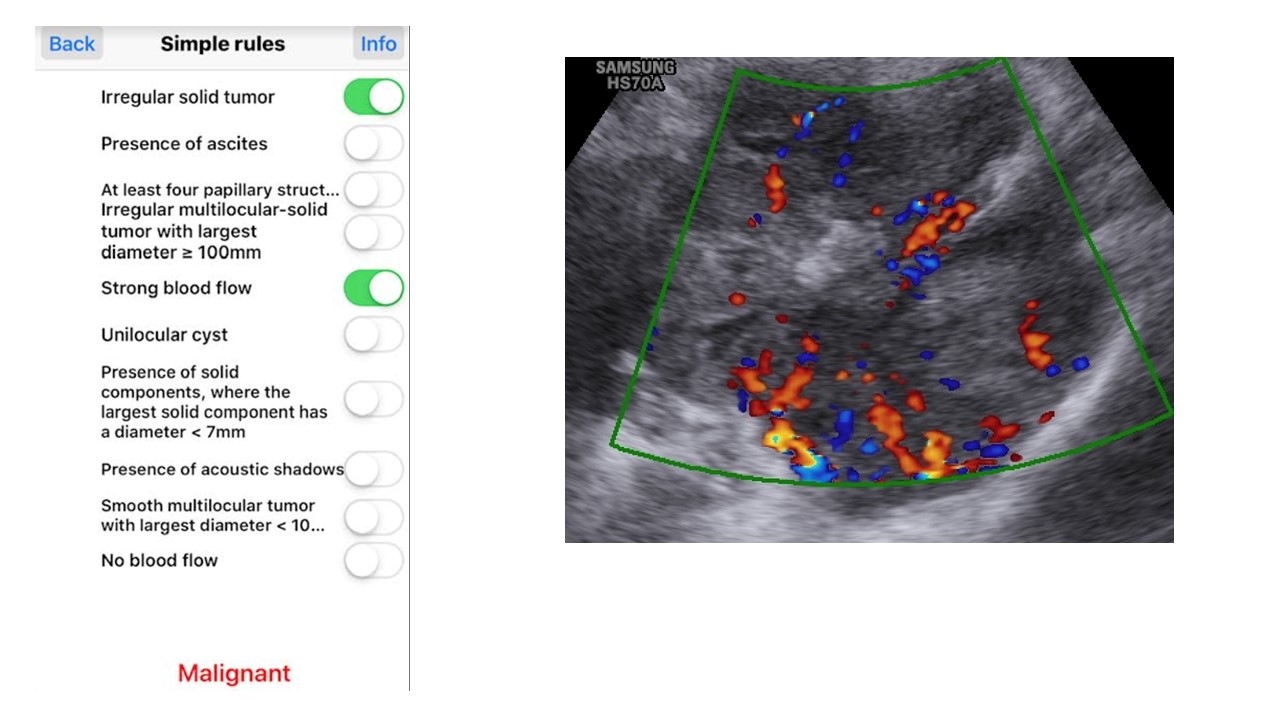

Tiếp cận chẩn đoán và phân tầng xử trí khối u buồng trứng theo IOTA-ORADS

Từ khóa: Tiếp cận chẩn đoán và phân tầng xử trí khối u buồng trứng theo IOTA-ORADS